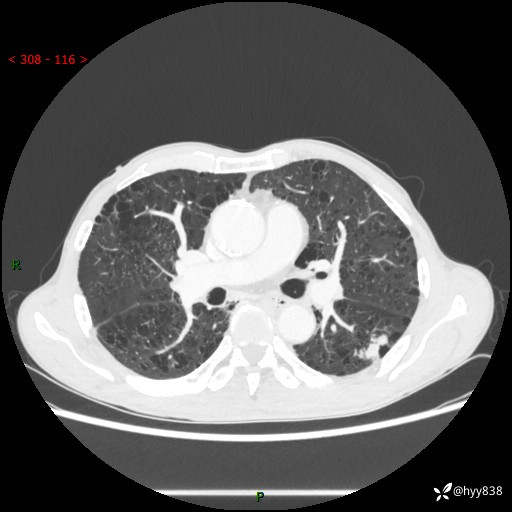

73岁/男,发现肺占位1月余。肺气肿背景,是否恶性倾向---结果公布~

现病史:患者于1月余前无明显诱因出现背部疼痛不适,无明显咳嗽、咳痰、胸闷、咯血、发热等不适,后于2024.5.3至当地市人民医院行胸部CT示:左肺下叶结块,大小约2.2cm*2.6cm,双肺多发小结节,双肺感染性病变,部分纤维增值灶,慢支并双肺局限性肺气肿,肺大泡,纵隔淋巴结增大并部分钙化,冠脉区及大血管壁钙化,双侧胸膜局限性增厚;后口服莫西沙星2周。2024.6.12复查胸部CT示:左肺下叶结块影形态较前饱满,较大截面范围约2.8cm*2.3cm,边缘可见细短毛刺及分叶,性质待查。现患者为求进一步诊治来我院,门诊以“肺占位”收入我科。 起病来,患者精神、食欲、睡眠尚可,大小便正常,体力体重轻微下降。

胸部CT平扫+增强

各期CT值:48hu 100hu 78hu